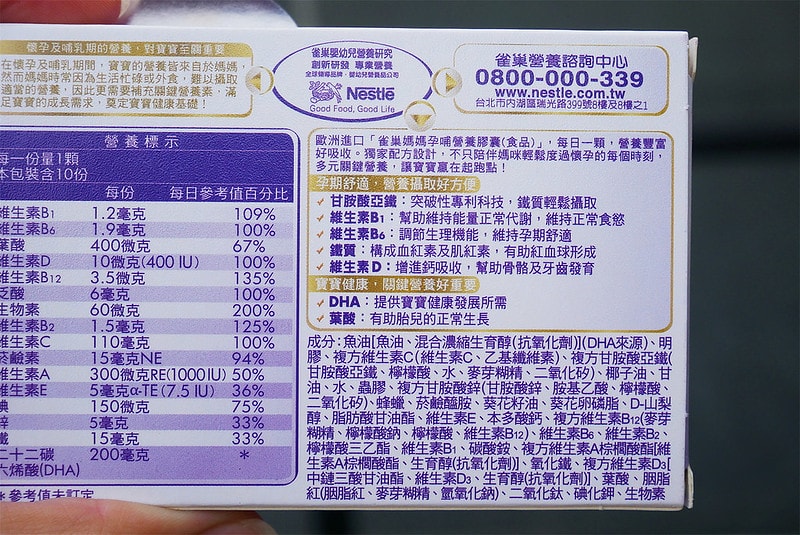

營養標示包裝上都寫得很清楚喔

比方說孕期最需要的鐵、DHA、葉酸、綜合維生素等

裏頭都有包含到唷

一顆裡面有葉酸、B群等綜合維他命、足量DHA、甘胺酸亞鐵等孕期關鍵營養,

甘胺酸亞鐵的突破性科技,更可以輕鬆幫助鐵質攝取

可滿足各階段關鍵營養需求,適合備孕、懷孕初、中、晚期以及哺餵母乳的媽媽。”